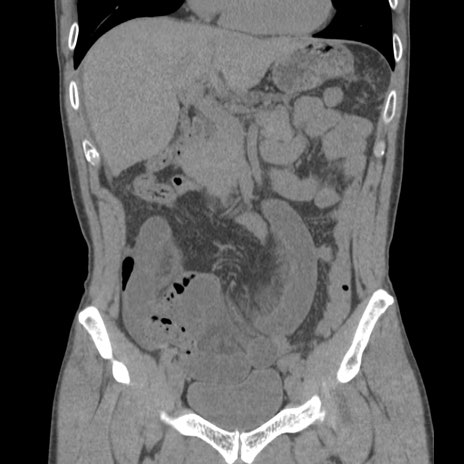

症例56 CT(冠状断像)

横断像